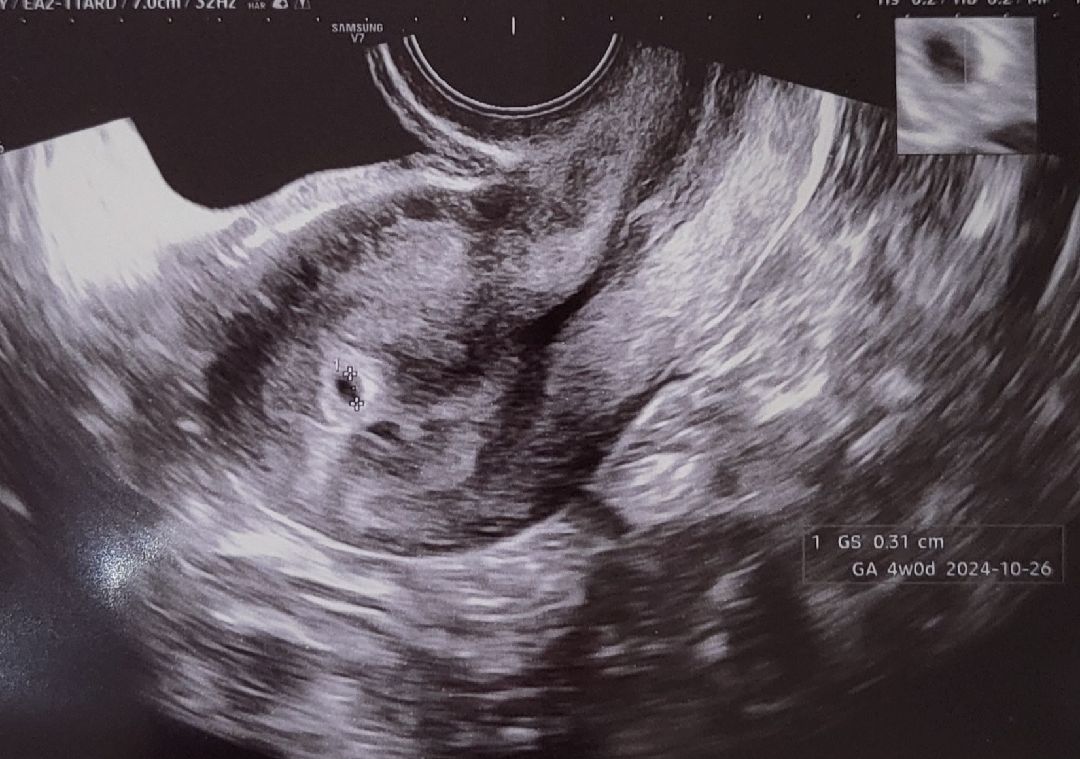

4주3일차 아기집 보고왔어요!

막생 1월17일 2월 13일에 처음으로 얼리 진한두줄보고 멋모르고 바로 산부인과갔다가 못보고돌아와서 오늘 아기집 보고왔습니다! 처음간 산부인과에서는 안보일거라고 진료도 못봤는데 혹시나하는 마음에 다른곳 찾아갔는데 보이더라구요!

감사합니다! 아주조그매요ㅎㅎ 3미리ㅎㅎ 귀엽고 예쁜 애기집 보고오세요!♡.♡